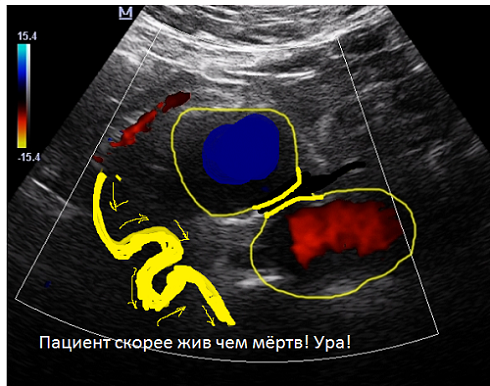

Описание ему не дали, а он собирается ехать завтра в область на коронарографию.

В общем я сердобольный, взял пациента на УЗИ аорты, хоть пациент сказал, что не готовился на это исследование и вот, что нашел:

Ваше мнение коллеги!

Вообще похоже на расслаивающуюся аневризму брюшного отдела аорты. Если уже на 90% расслоившуюся.

Извитость, атеросклеротической аорты да неравномерной по диаметру да в разных местах аневризматически расширенной, но опять же неравномерно описала бы увиденную картину в более спокойных тонах!

то что вы тут усиленно рисуете - ложный канал в тромбе